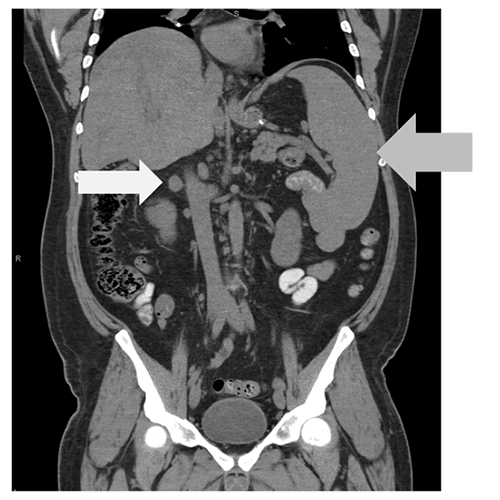

Figure 1. Abdominal CT Scan Reveals Splenomegaly (19 cm, gray arrow) and Lymphadenopathy (white arrow). Published with Permission

Three weeks following discharge, the patient presented again with persistent abdominal pain, nausea, low-grade fever, and leukocytosis of 10.9/nL). CT demonstrated a small perigastric fluid collection, splenomegaly, and prominent abdominal and retroperitoneal lymphadenopathy. Based on the prior pathology findings and the new CT scan demonstrating lymphadenopathy, the patient was admitted for consultation with rheumatology and diagnosed with active sarcoidosis. Treatment with prednisone and methotrexate was initiated on an outpatient basis.

Three months after surgery, the patient presented to the emergency department again with new laboratory abnormalities: leukopenia (white blood cell count of 2.4) and elevated liver function tests (alkaline phosphatase 203, alanine transaminase 88, aspartate transaminase 51) with abnormal bilirubin levels. A repeat CT scan demonstrated a splenomegaly compared to prior studies (Figure 2).

Despite cholecystectomy, his abdominal symptoms and laboratory abnormalities persisted. Repeat imaging showed increased splenomegaly (18 cm to 19 cm). Hematology recommended a splenectomy to address the persistent leukopenia and rule out malignancy. Laparoscopic splenectomy was performed by the original surgeon ten months after the gastric sleeve procedure. Sarcoidosis was confirmed on pathology.